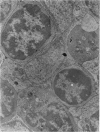

Images in this article